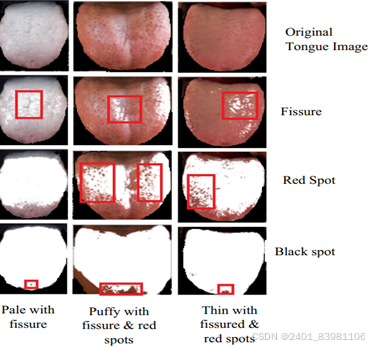

形质识别:现状:特殊如齿痕,腐腻等不能全面分析。针对齿痕、裂 纹等单一形质特征的研究较深入:

舌象分类

- 运用深度残差神经网络ResNet(AB-ResNet18等变种更高)(对齿痕舌进行识别,准确率达90%,对腻苔的识别分类准确率超过88%,使用加权梯度类激活映射技术对识别齿痕的图像特征区域进行可视化分析。

- 应用预训练的卷积 Inception_v3模型提取舌象点、线等有效特征,再使用 全连接神经网络对特征进行训练分类,分类准确率可达93.98%。

问题:各类算法准确率高,但局限(如多任务CNN的舌象分类模型特征不全面),采用多目标检测算法但不能高效益(如迁移Faster R-CNN模型针对语言分类训练中深度学习中训练设备要求高、训练时间长等问题提出)

综合: 高效精准识别、定位、量化复杂多样的舌象形质细粒度特征是重点